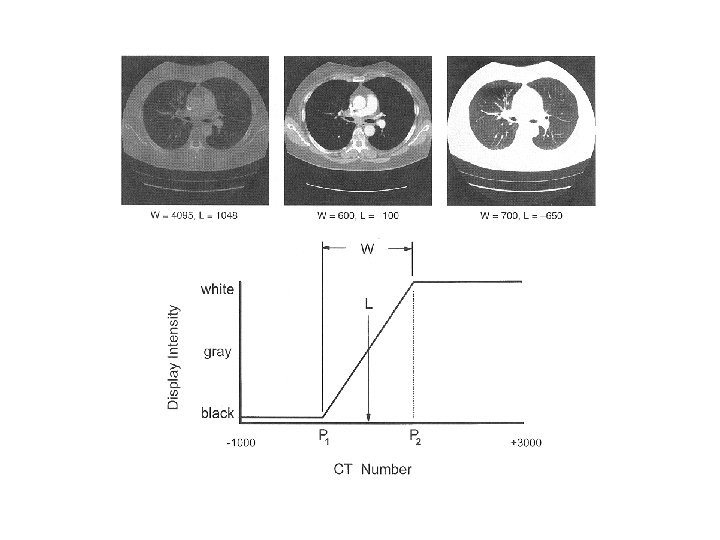

CT numbers or Hounsfield units • The number CT(x, y) in each pixel, (x, y), of the image is: • CT numbers range from about – 1, 000 to +3, 000 where – 1, 000 corresponds to air, soft tissues range from – 300 to – 100, water is 0, and dense bone and areas filled with contrast agent range up to +3, 000

Digital image display • Window and level adjustments can be made as with other forms of digital images • Reformatting of existing image data may allow display of sagittal or coronal slices, albeit with reduced spatial resolution compared with the axial views • Volume contouring and surface rendering allow sophisticated 3 D volume viewing